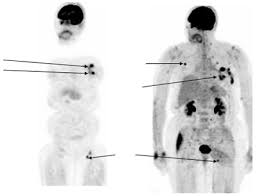

* Swollen lymph nodes